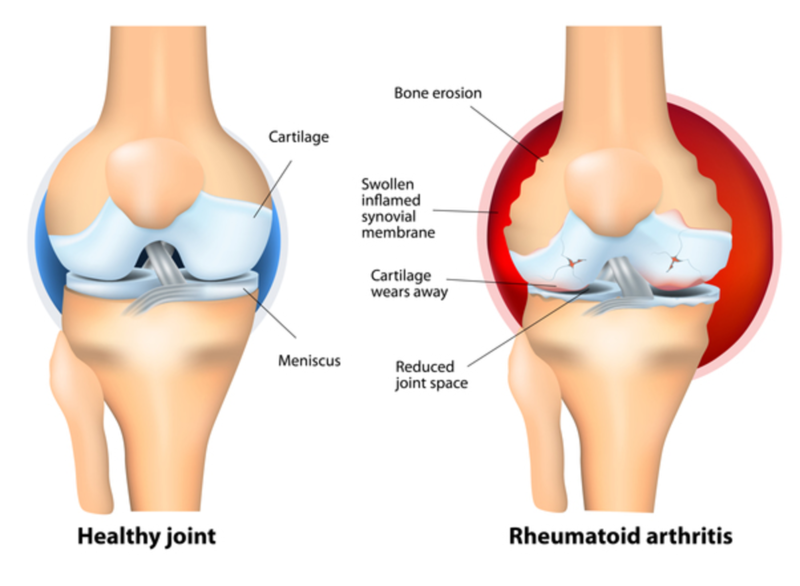

Arthritic changes – Arthritis is related to a condition of painful joints due to inflammation or swelling. A type of arthritis is rheumatoid arthritis, it is an autoimmune disease where the immune system attacks the joints, starting with the lining of joints. Rheumatoid arthritis is heavily related to lung problems, about 80% of arthritic patients have lung-related issues, making it the second leading cause of death with rheumatoid arthritis patients. Rheumatoid arthritis caused lung problems are most commonly extra-articular i.e., outside of the joints and involves pulmonary nodules; damage to the lung airways, pleural effusion and interstitial lung disease. In rheumatoid arthritis associated interstitial lung disease the auto-immune system gets over active and attacks the lungs and causes scarring. With time, the scarring build-up leads to difficulty breathing and reduced lung function.